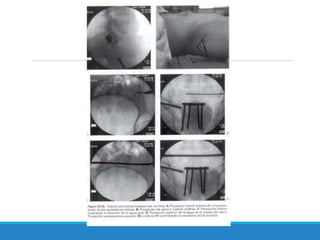

Este documento describe las fracturas de pelvis, incluyendo su etiología, mecanismos, clasificación y tratamientos. Las fracturas de pelvis se clasifican según el sistema de clasificación de Tile, que categoriza las fracturas como Tipo A, B o C dependiendo de su estabilidad y ubicación. El tratamiento depende de la clasificación Tile, con reposo para el Tipo A, estabilización del anillo anterior para el Tipo B, y estabilización anterior y posterior para el Tipo C.